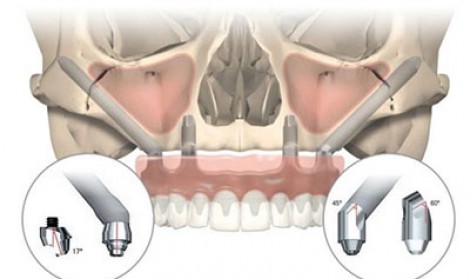

ایمپلنت های زیگوماتیک طولانی تر از ایمپلنت های دندانی طبیعی می باشند و به جای تکیه بر فک بالا، از طریق فضای سینوسی وارد استخوان زیر گونه یا استخوان زایگوما می شوند. پس از ثبات بسیار خوبی در فک برخوددار است .

استفاده ازاین روش در انتهای دهان به همراه دو ایمپلنت معمولی در جلوی دهان استفاده می شود.

البته روش درمانی طولانی تر از ایمپلنت های معمولی است و از استخوان بزرگ و حجیم گونه برای محکم کردن در فک استفاده می شود.

در این روش ایمپلنت ها بجای اینکه در استخوان فک کاشته شوند از مجاوت سینوس ها عبور کرده و در استخوان گونه کاشته می شوند . به همین دلیل طول ایمپلنت از ایمپلنت های استفاده شده در روش های دیگر بیشتر است .